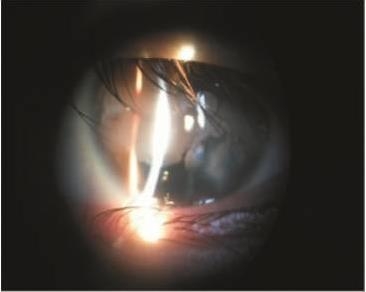

术后第1天复查时,患者刺激症状较重,但已能短暂睁 眼配合检查,查角膜上皮 3 mm 范围缺损,切削区角膜较术前清亮,带状变性明显减轻(见图 4),可见前房硅油,玻璃体大量增殖,视盘界清、色正,颞侧视网膜脱离,诊断为左眼增殖性玻璃体视网膜病变,多次视网膜脱离修复术后。完善相关检查,随即收入院。

2014年12月31日在全身麻醉下行左眼硅油取出、视网膜切开、视网膜下硅油取出、剥膜、激光、硅油填充术,术后嘱俯卧位。术后 7 d 眼科检查:左眼视力 0.03,眼压 11 mmHg, 角膜 8.5 mm范围内光学区尚清亮光滑,玻璃体腔硅油填充,眼底检查:视盘界清、色正,视网膜在位(见图 5)。随后患者出院。

A,术前;B,术后

图 5 左眼角膜带状变性患者手术前后眼底像